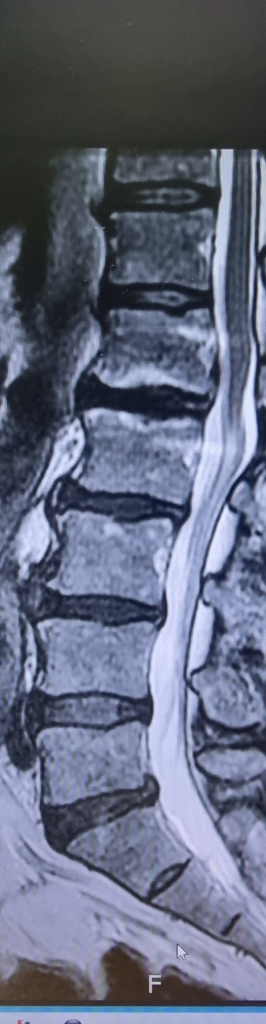

디스크가 약간 튀어나와있긴 하지만 비가역적인 변화가 생기지는 않은것으로 판단됩니다.

디스크의 정식 병명은 추간판 탈출증으로 추간판의 수핵이 탈출하여 신경을 압박함으로서 나타나는 일련의 증상입니다. 추간판 탈출증의 경우 시간이 지나면서 돌출된 수핵은 면역기전에 의해 저절로 줄어들어 증상이 완화되는 경우도 있습니다. 하지만 신경학적 이상이 동반되거나 경우에 따라 빠른 감압술이나 수술이 필요할 수도 있으므로 주치의와 상의하시는 것이 좋겠습니다.